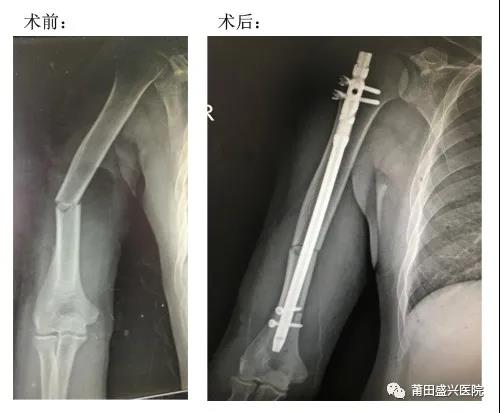

近日,我院骨科成功開(kāi)展兩例微創(chuàng)治療肱骨中段骨折手術(shù),患者術(shù)后恢復(fù)良好,均已順利出院……